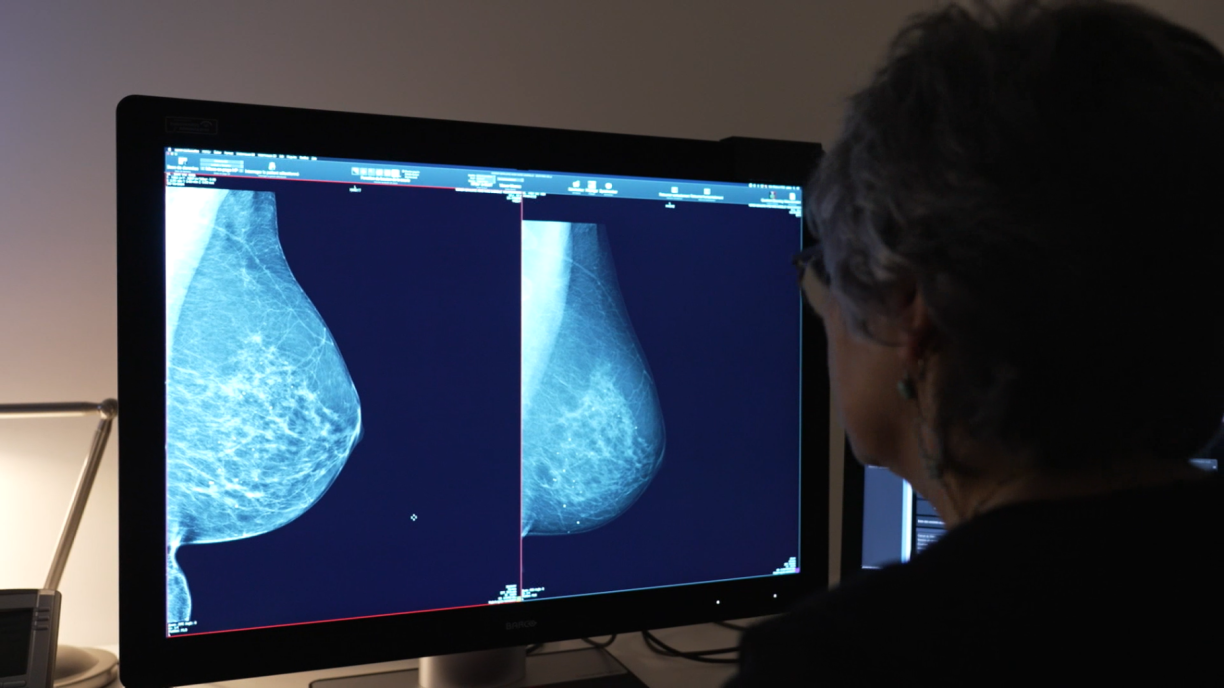

Grâce à ce programme, des femmes peuvent passer gratuitement une mammographie tous les deux ans. Les images radiographiques sont évaluées deux fois: une première fois par le radiologue de l’hôpital, une deuxième fois par un autre radiologue du service de santé. Si nécessaire, un troisième contrôle peut également avoir lieu.

Ce système de double contrôle permet de dépister +/- 20% de nouveaux cas en plus, selon Fanny Lorin. Malheureusement, le nombre de participantes au programme a légèrement reculé ces dernières années, d’après la responsable du service.